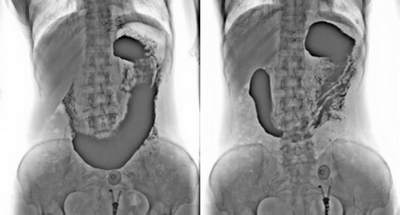

3. 數字化胃腸:

★消除普通數字胃腸機視野小的缺陷,直接獲得大視野全數字化圖像 (17x17) 。

★更加方便胃腸、食管、上消化道、全消化道等造影功能!